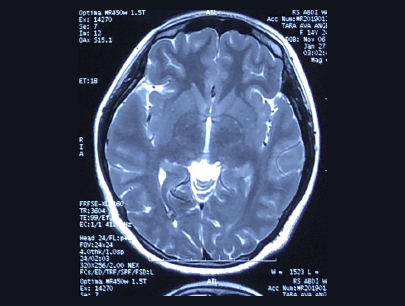

(Perempuan 22Tahun)

Diagnosis: Tumor Pineal

Sebelum Gamma Knife

• Nyeri Kepala

• Pandangan Ganda

• Gangguan Gerak Bola Mata

3 bulan Setelah Gamma Knife

• Pandangan ganda tidak ada

• Gangguan gerak bola mata perbaikan

Catatan: pasien menjalani operasi VP Shunt

Volume Tumor: 25,7 cc

Volume Tumor: 3 cc